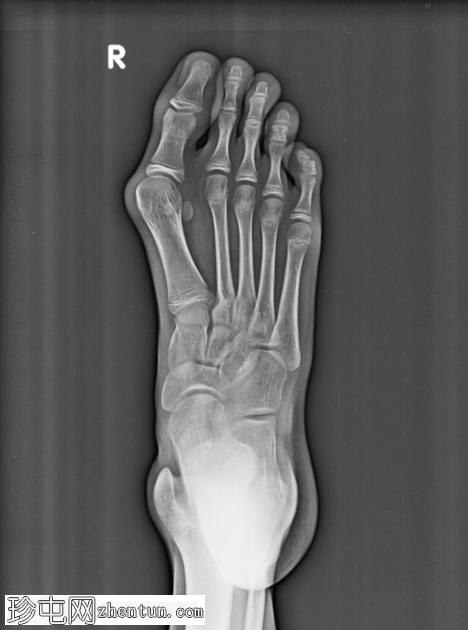

正位片

第一跖趾关节处拇趾(拇趾)向外侧偏斜。第一跖骨向内侧偏斜,导致拇外翻角增大。近节趾骨相对于第一跖骨头轻度向外侧半脱位。第一跖骨头内侧隆起,呈圆形。

未见急性骨折或脱位。其余可见的跖骨和趾骨排列正常。未见骨侵蚀或局灶性破坏性病变。